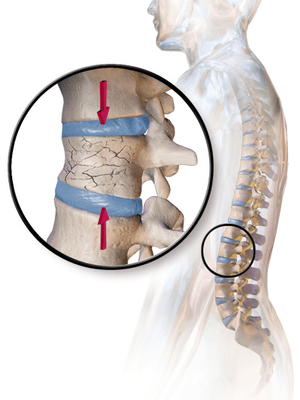

A compression fracture is a collapse of a vertebra. It may be due to trauma or due to a weakening of the vertebra (compare with burst fracture). This weakening is seen in patients with osteoporosis or osteogenesis imperfecta, lytic lesions from metastatic or primary tumors,[1] or infection.[2] In healthy patients it is most often seen in individuals suffering extreme vertical shocks, such as ejecting from an ejection seat. Seen in lateral views in plain x-ray films, compression fractures of the spine characteristically appear as wedge deformities, with greater loss of height anteriorly than posteriorly and intact pedicles in the anteroposterior view.[3]